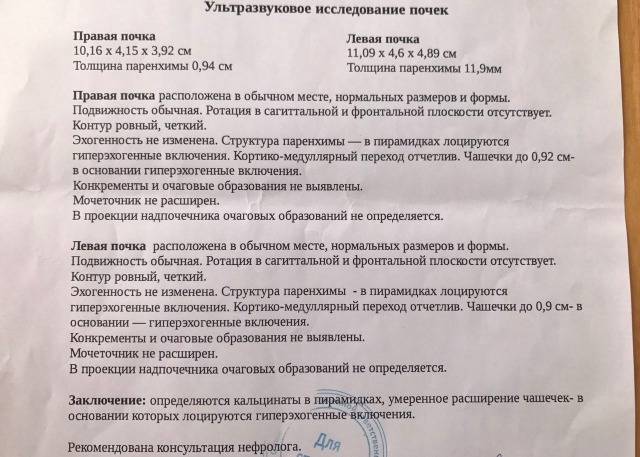

Раздел: Снимки-откровения